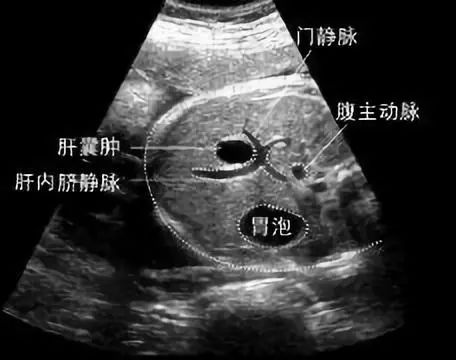

通俗地说,肝囊肿就是肝脏上的水泡,一般不和外面相通,位置较浅或个头大的,可突出来,使肝表面变得不光滑。

但是多数就是几毫米到几厘米大,可以是一个,也可以是好几个,内部结构可以是‘单间’,也可是‘套间’,囊内还会有液体,所以看起来就像个水泡。

超声是最有效的初检手段,如果需要进一步鉴别,可以再做CT或者核磁共振,甚至穿刺针吸活检等检查。CT如下图所示

最常见的单纯性肝囊肿,在超声检查中表现为肝脏内部出现的澄清液体的囊性结构,偶然体检发现的无症状患者不需要对肝囊肿进行治疗,单纯性肝囊肿也不需要反复做检查。